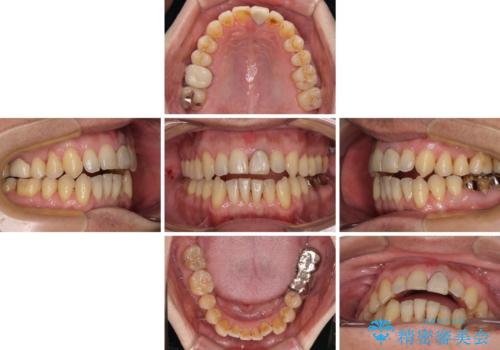

奥歯の銀歯は、土台の一部に抜歯が必要であったので、矯正治療の途中で抜歯してからオールセラミックブリッジによる補綴治療を行うこととしました。